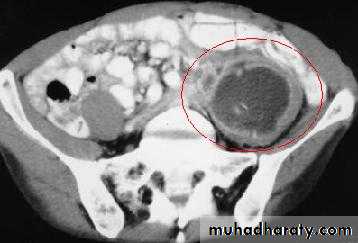

Retroperitoneal tumor

Peritoneal cavity and retroperitoneal